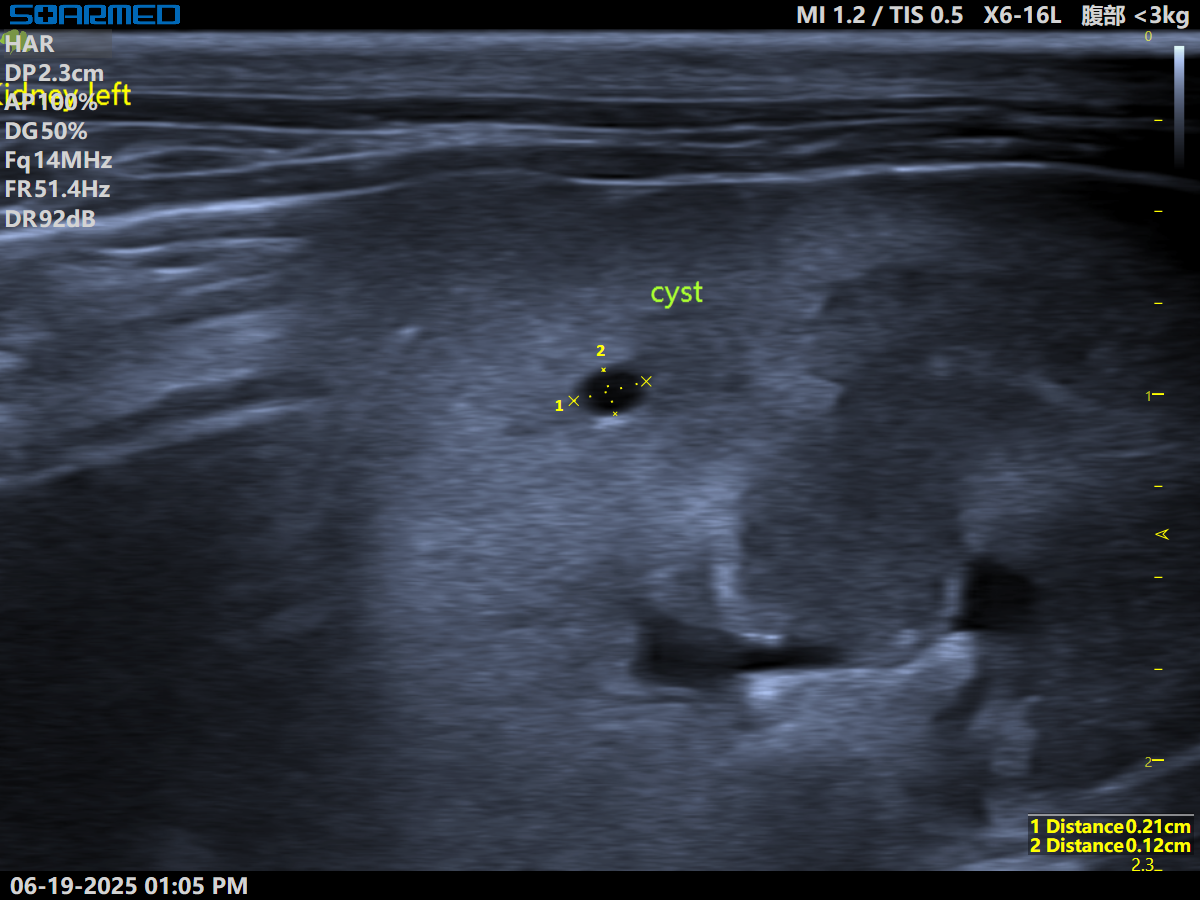

LK-1.png